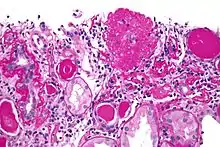

| Light micrograph of focal segmental glomerulosclerosis, hilar variant. Kidney biopsy. PAS stain. | |